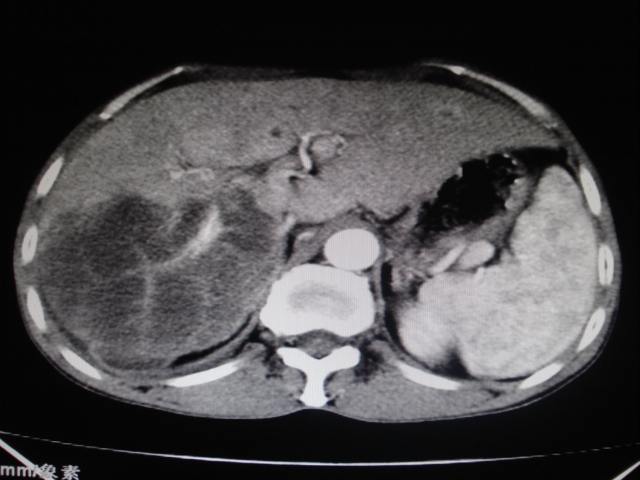

标题: CT24041:肝脏占位,请会诊!

男性,62岁。肝右叶占位,平扫及增强如下,延迟期为15分钟扫描。